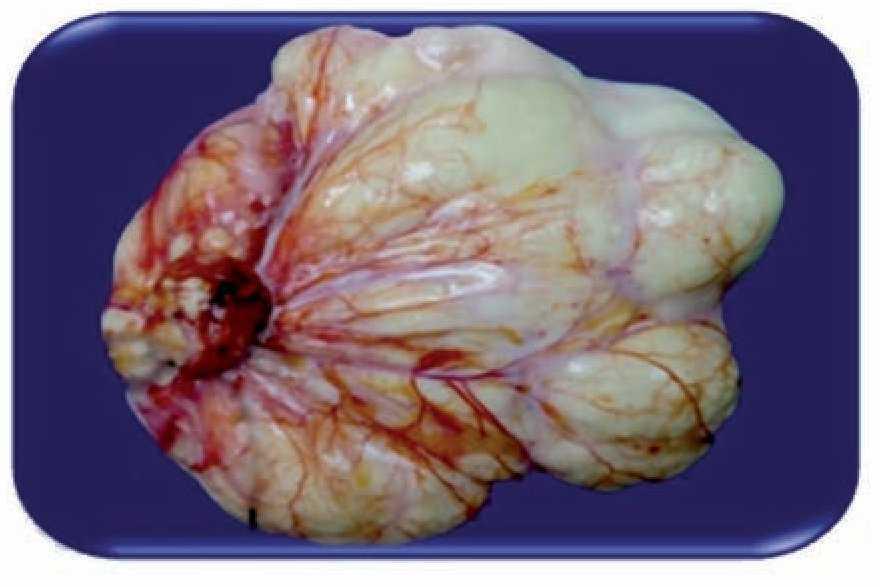

Mujer de 82 años de edad, que durante los 10 años previos presentaba dolor abdominal recurrente e intolerancia a la vía oral. En el último año se agregó pérdida de peso de aproximadamente 10 kg y una masa abdominal en flanco derecho, con aumento progresivo de tamaño. Al examen físico se palpó masa de aproximadamente 10 cm por 8 cm, móvil, indurada, de bordes irregulares. El ultrasonido (USG) abdominal mostró una lesión quística hipocoeica, multiseptada, ubicada en el cuadrante superior derecho, probablemente dependiente de hígado. La tomografía computarizada (TC) de abdomen mostró una lesión quística de aproximadamente 14 cm, de aproximadamente 14 unidades Hounsfield (UH) por debajo del hígado y delante del riñón derecho, condicionando desplazamiento del colon derecho (Figura 1). Se realizó una laparotomía exploradora, encontrando un tumor quístico retroperitoneal, adherido al mesocolón transverso y páncreas, el cual midió 15 cm por 10 cm por 5 cm. La pared del quiste era blanquecina y muy vascularizada (Figura 2). La lesión fue resecada completamente y su evolución sucedió sin complicaciones por lo que fue egresada por mejoría. El examen histopatológico confirmo un linfagioma retroperitoneal (Figura 3).

¿ Figura 2. Vista macroscópica, de la lesión quística retroperitoneal, resecada completamente, multiquística, muy vascularizada de 15 cm por 10 cm por 5 cm de contenido quiloso.